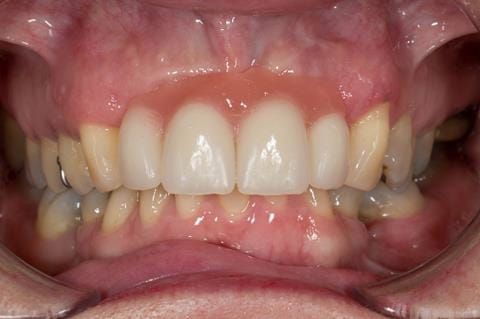

- High smile line showing gum above gingival zeniths of upper front teeth when smiling. Aesthetic failure of the upper four incisors with inflammation of the gingivae and mis-match of the gingival zenith levels.

- Extract the upper 2-2 teeth and replace with an interim acrylic based partial denture. Reline the interim denture over 9 - 12 months, replacing with a definitive cobalt chromium based partial denture. The definitive denture would ideally be designed as an occlusal protective splint to reduce the the potential for mechanical wear and breakages of the moderately/heavily restored maxillary dentition. In addition, should further upper teeth require extraction they could be added on to the denture cobalt chromium framework - therefore a new prosthesis would not be required as future teeth are lost. This option would produce an excellent aesthetic outcome. This is the option the patient chose to have.

Following consultation and second discussion appointment the patient chose to have option 3 namely, a maxillary cobalt chromium based partial denture/protective occlusal splint. The clinical situation and treatment process is shown in detail below with photographs. The patient was successfully rehabilitated with this and her quality of life considerably improved. The clinical work was provided by Finlay and the technical work by Rowan.